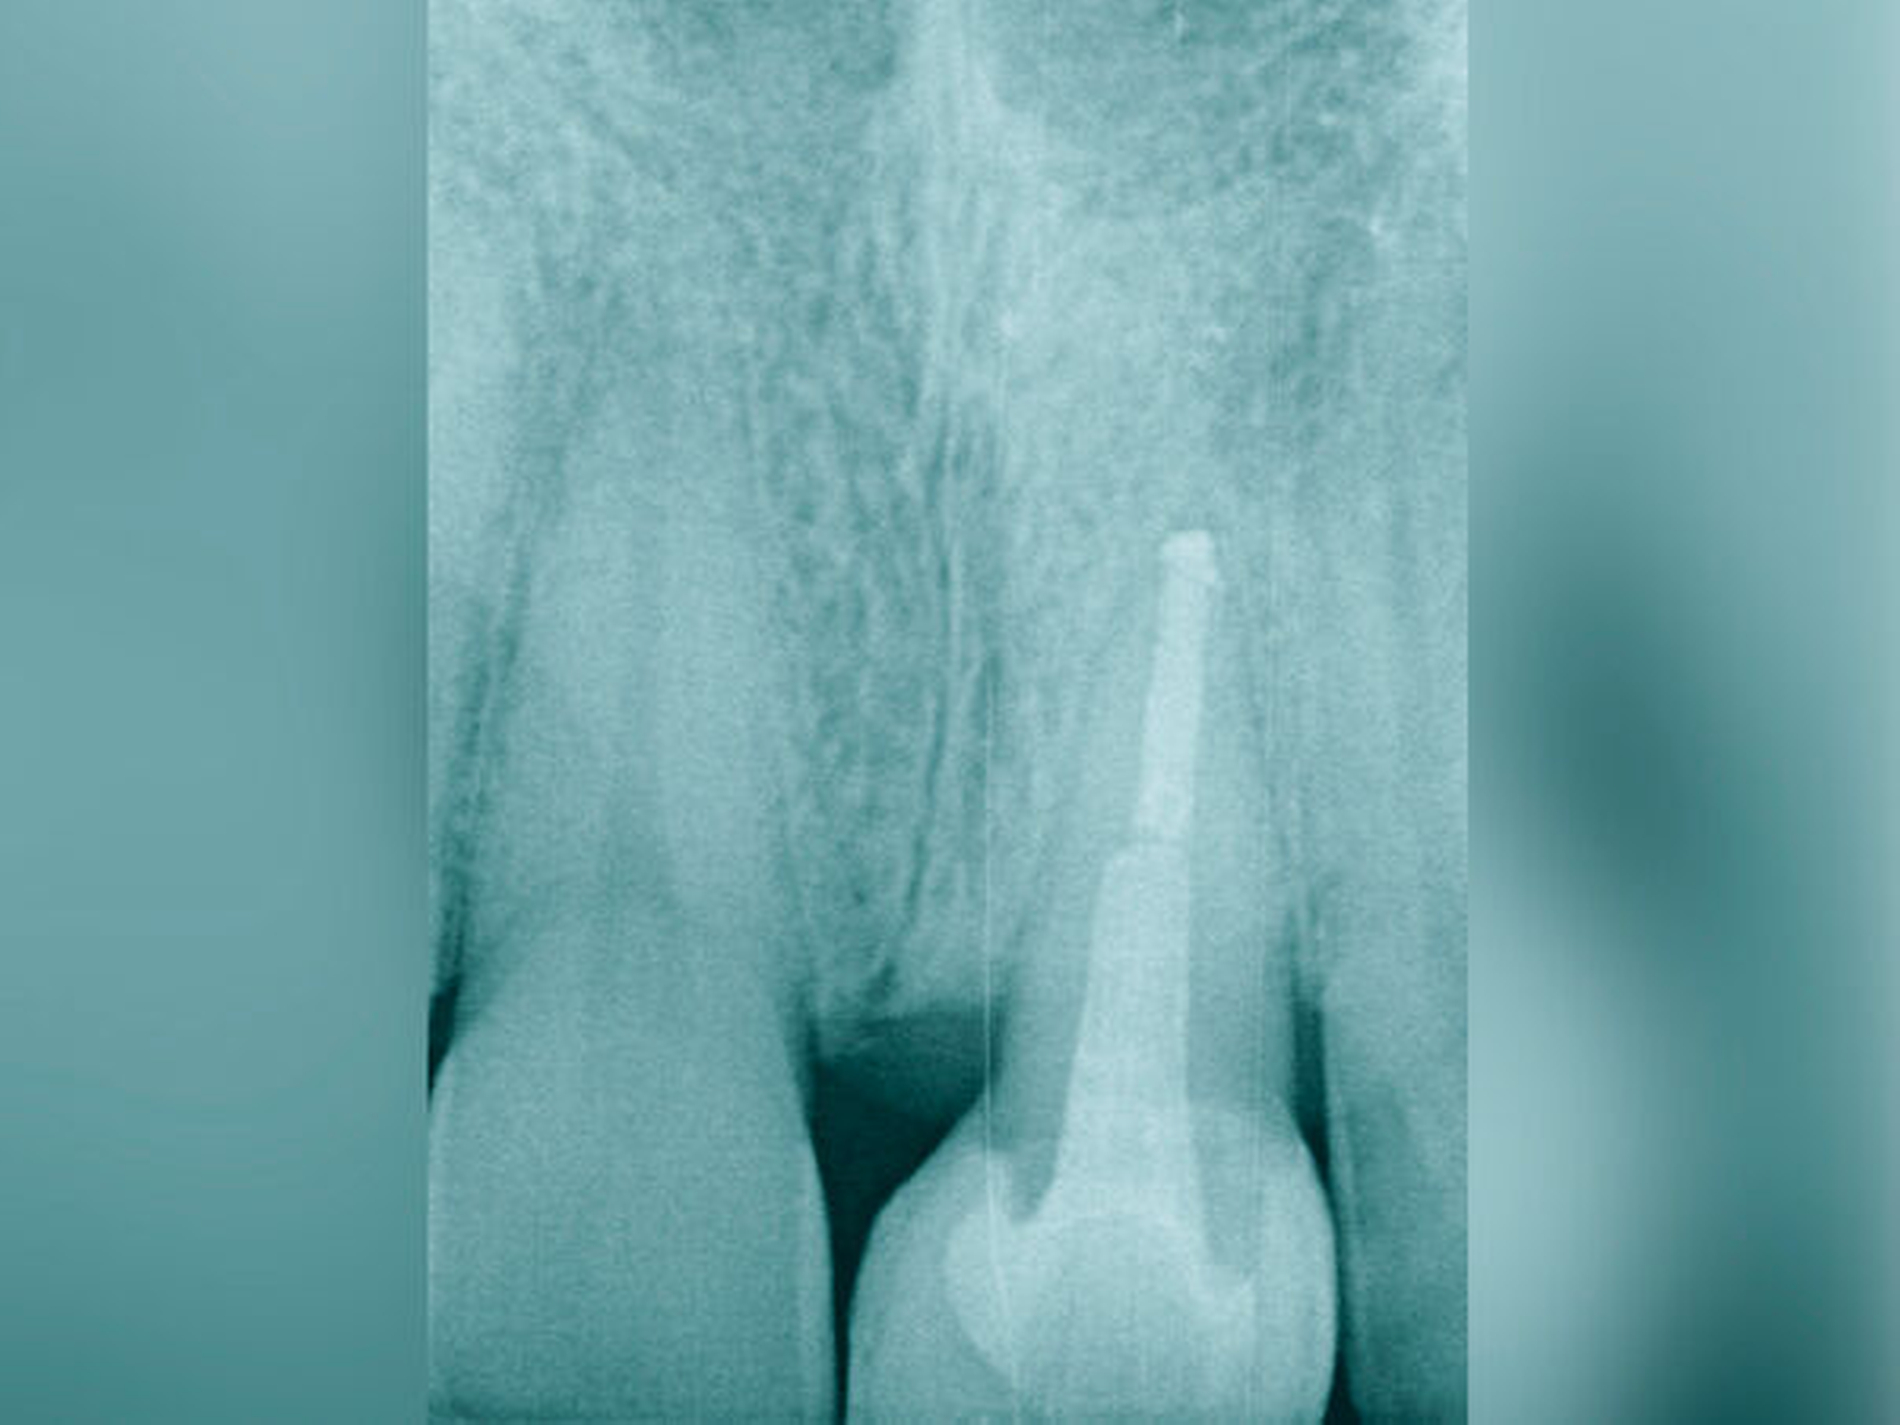

Bei der chirurgischen Extrusion (Synonym: intra-alveoläre Transplantation) wird der betroffene Zahn oder die betroffene Wurzel chirurgisch weiter koronal positioniert, um die Anfertigung einer adäquaten Restauration zu ermöglichen. Ihr biologisches Prinzip ist eingehend beschrieben worden mit guten Erfolgen im Tiermodell [Oikarinen et al., 1996] und in der klinischen Anwendung [Caliskan et al., 1999; Das und Muthu, 1999; Krug et al., 2018]. Die Technik wird bisher kaum in der zahnärztlichen Praxis angewendet, vermutlich aufgrund der begrenzten Vorhersagbarkeit, einen schwer kompromittierten Zahn oder eine Zahnwurzel erhalten zu können, wenn auf konventionelle Art und Weise extrahiert wird. Zum einen besteht das Risiko, durch die Extraktion eine Zahnfraktur zu verursachen, die den Zahnverlust zur Folge hat. Zum anderen führt die Anwendung von Luxatoren, Elevatoren oder Periotomen zu einer Aufdehnung der Alveole sowie zu Schäden am parodontalen Gewebe und gegebenenfalls an der Zahnwurzel selbst. Die Herausforderungen bei einer Zahnmobilisation für eine chirurgische Extrusion bestehen darin, weiteren Schaden an den Strukturen von Zahnhartsubstanz, Knochen und parodontalem Ligament zu vermeiden. Gelingt dies, können deren Hauptrisiken wie Zahnfraktur und progressive Wurzelresorption minimiert werden [Elkhadem et al., 2014].

Zur chirurgischen Extrusion werden meist Extraktionszangen verwendet. Die Zahnwurzel wird dabei idealerweise mit einer diamantierten Zange gefasst und durch Rotation vorsichtig entfernt. Insbesondere bei Zähnen mit runden Wurzeln ist diese Technik auch weitgehend schonend für das parodontale Ligament. Der forcierte Einsatz von Hebeln oder Luxationsbewegungen ist zu vermeiden, da diese zu parodontalen Schäden auf der Wurzeloberfläche führen können und somit die parodontale Heilung nach Replantation gefährden.

Eine weitere Möglichkeit, tief zerstörte Zähne möglichst schonend chirurgisch zu extrudieren, basiert auf axialen Zugsystemen (Abbildungen 2 bis 4). Diese erscheinen vorteilhaft bei sehr schwierigen Fällen, zum Beispiel bei Zähnen mit fehlendem Ansatzpunkt für die Zange sowie bei langen oder sehr ovalen Wurzeln. Axiale Zugsysteme ermöglichen die Übertragung von Zugkräften auf die Zahnwurzel, ohne die Alveole unnötig zu dehnen. Dazu wird eine spezielle Schraube in den Wurzelkanal eingebracht und das Gewinde der Schraube für eine ausreichende Friktion fingerfest eingedreht. An diese Schraube wird ein gerätespezifisches Zugsystem angelegt. Durch rein axial wirkende Zugkräfte werden traumatische Effekte auf Knochen und Wurzeloberfläche während der Zahnmobilisation minimiert. Gegebenenfalls können feine Luxatoren vorsichtig unterstützend eingesetzt werden. Im Tiermodell wurde an extrahierten und wieder replantierten Zähnen mit ovalem Querschnitt gezeigt, dass der Verlust von Zementoblasten auf der Wurzeloberfläche geringer ist, wenn ein axiales Zugsystem anstatt einer Extraktionszange verwendet wird.